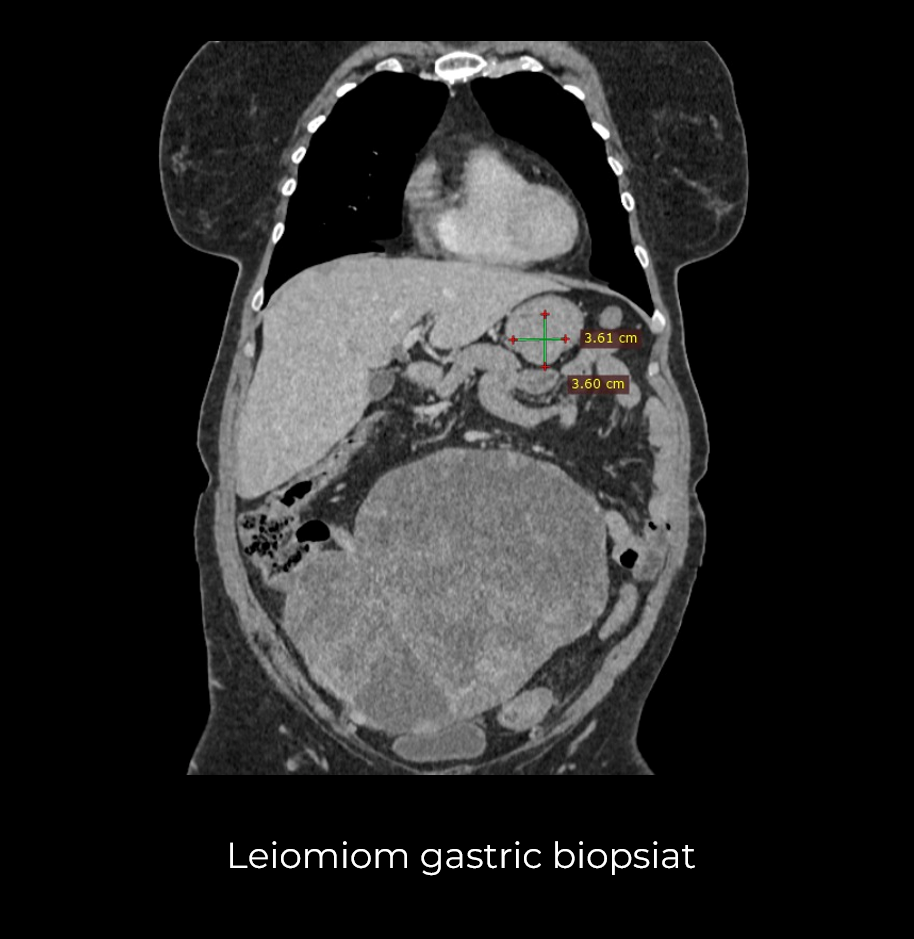

Uneori, o durere aparent banală ascunde în spate o realitate medicală mult mai serioasă. Așa s-a întâmplat și în cazul unei paciente de 63 de ani, care a ajuns la spital pentru dureri pelvine persistente. Investigația CT a schimbat însă complet perspectiva: au fost descoperite trei formațiuni tumorale în zone diferite ale corpului – o tumoră mamară stângă (carcinom mamar invaziv biopsiat), o tumoră pelvi-abdominală voluminoasă (tumoră ovariană) și o formațiune la nivelul peretelui posterior gastric (leiomiom gastric biopsiat).

- Gastrectomie segmentară – excizia porțiunii afectate din stomac